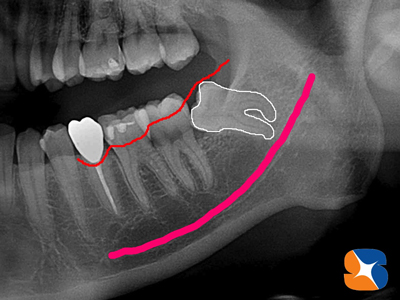

Dr:「横向きに生えている親知らずと隣り合わせの歯が重なり合い、そこに食べ物が挟まり続けて虫歯になったようです。

親知らずは、抜歯します。その隣りの歯は抜かずに残せますが、神経だけは抜く必要があります。点滴をしながら、一度に両方の治療を行いますので、がんばっていきましょう!

〈レントゲン画像〉横向きに生えている親知らずの歯と重なりあっている所に食べ物が挟まり、きつい痛みを伴う大きな虫歯になりました。